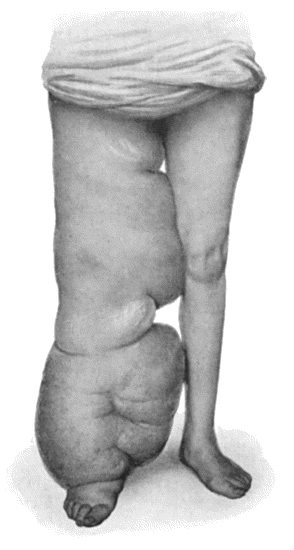

133.Skeleton of Rickety Dwarf 470

134.Changes in the Skull resulting from Ostitis Deformans 474

135.Cadaver, illustrating the alterations in the Lower Limbs resulting from Ostitis Deformans 475